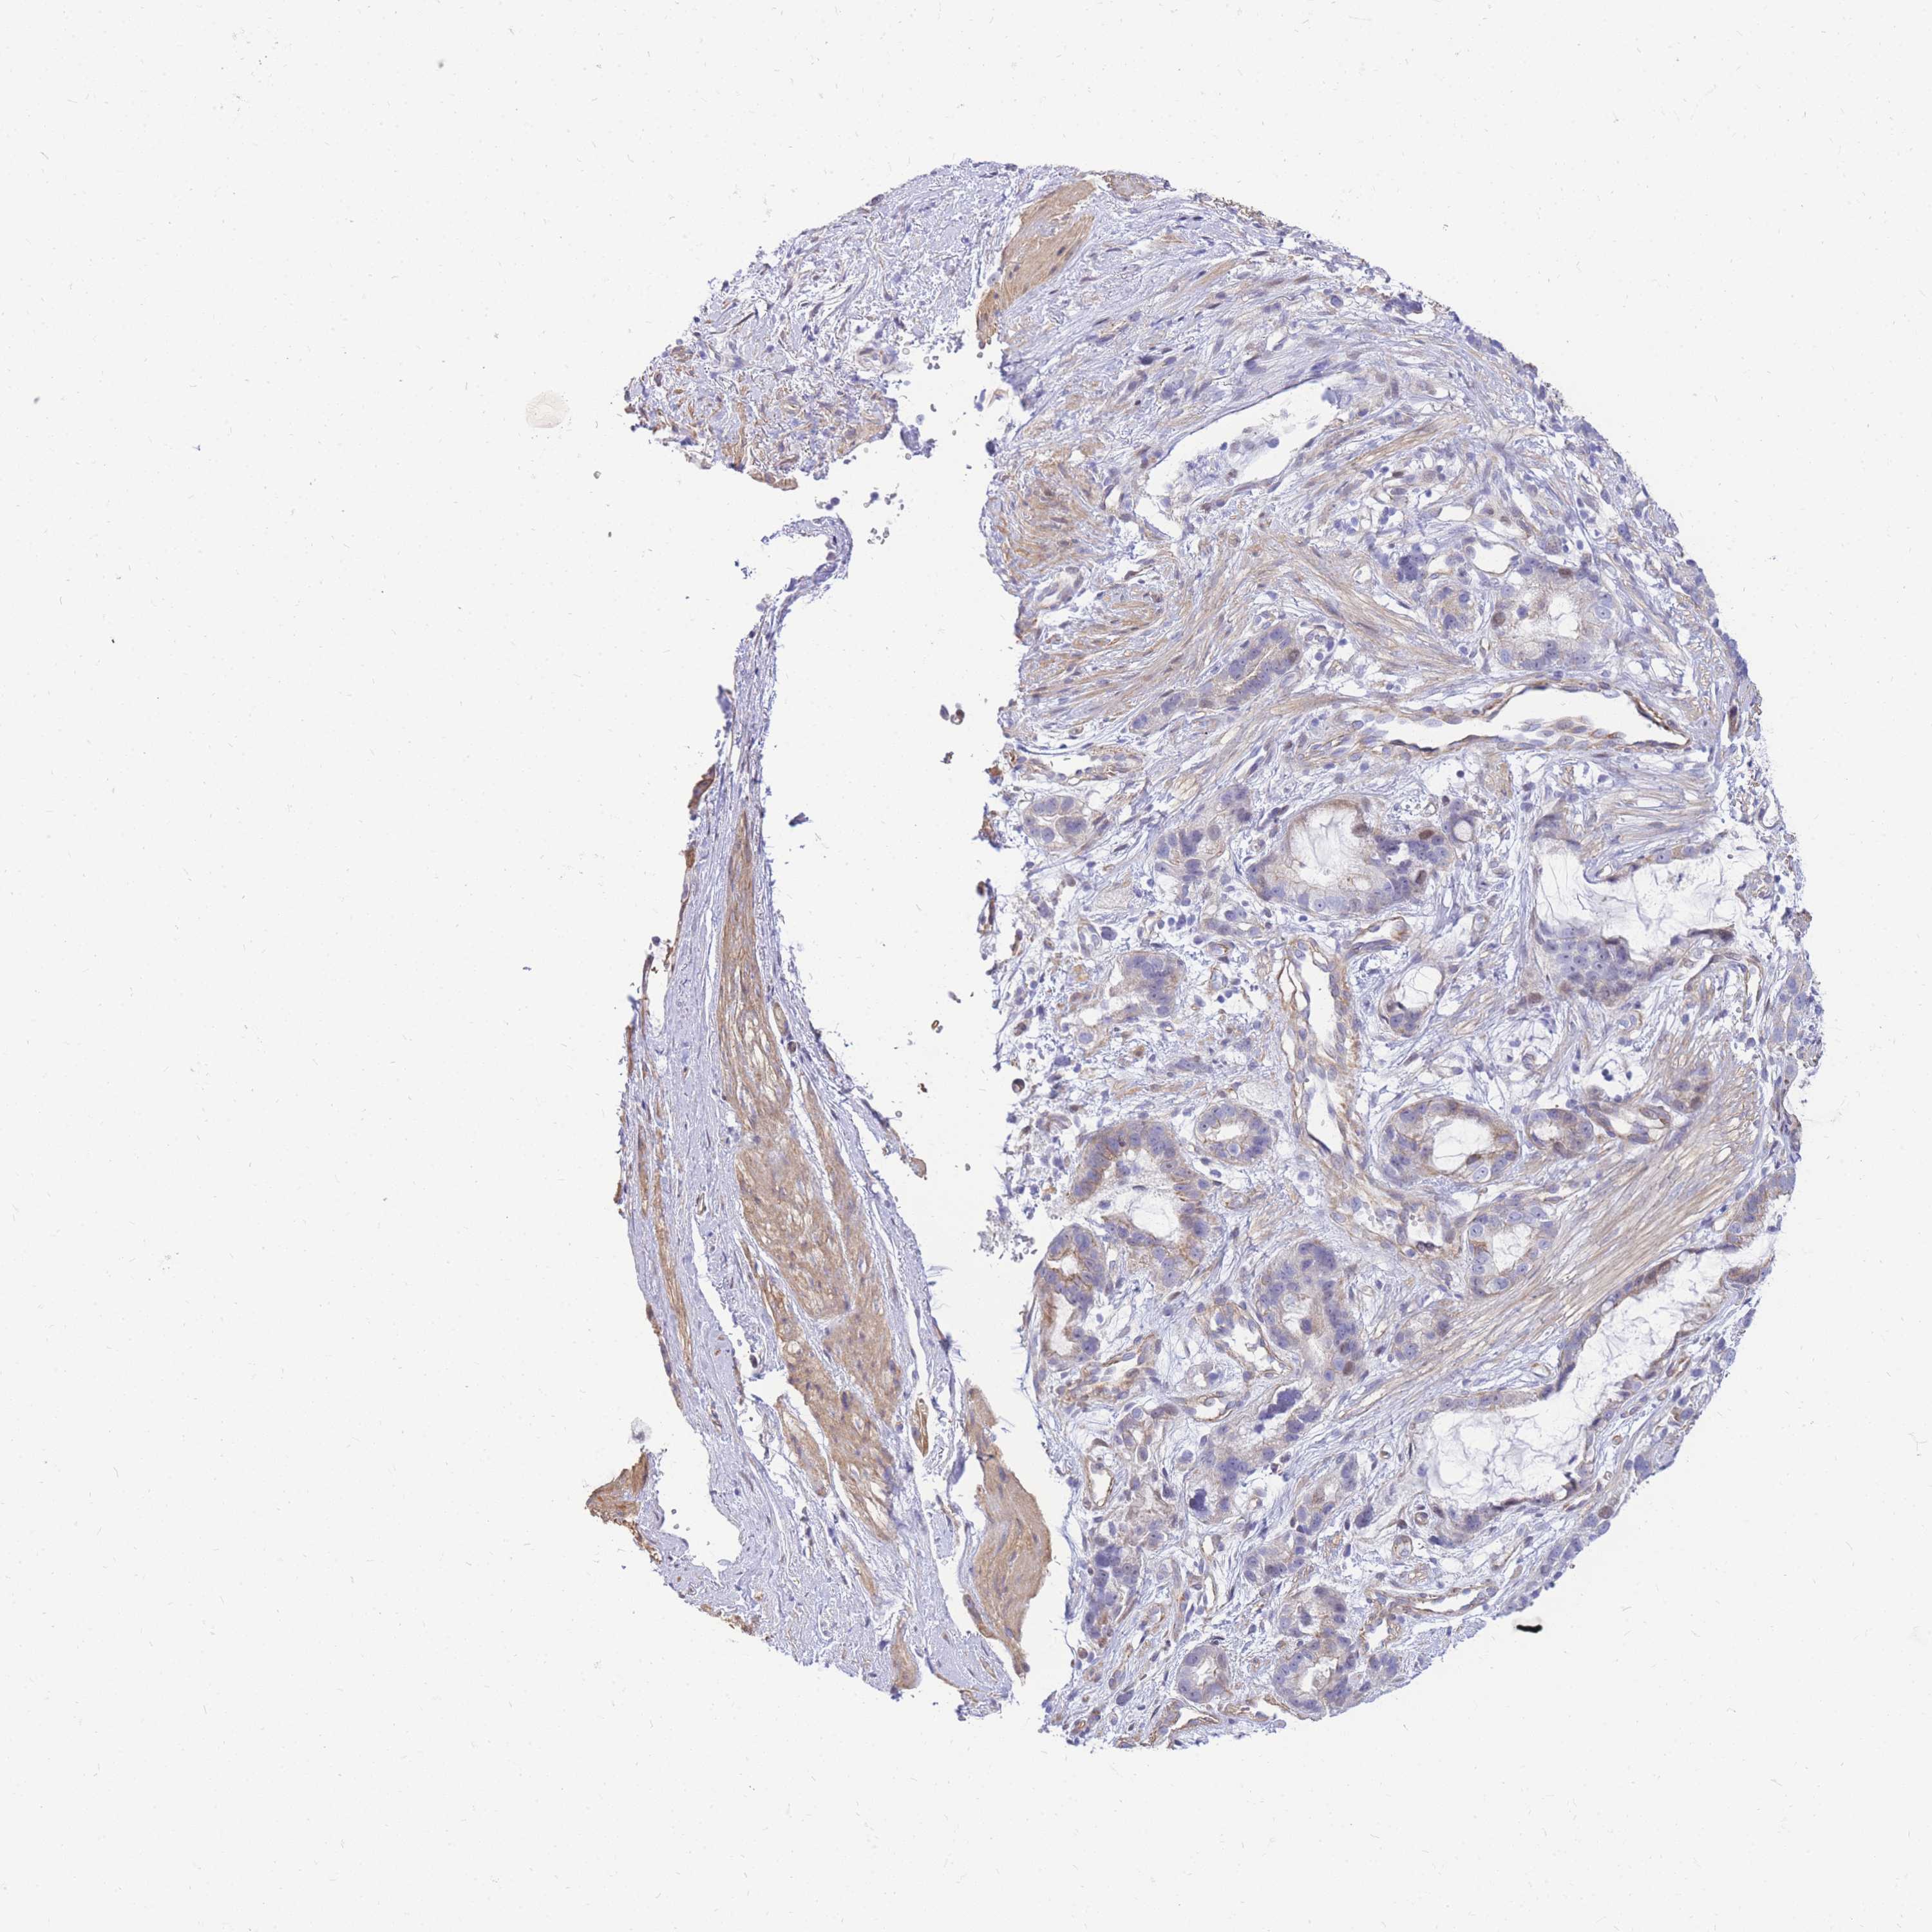

STOMACH CANCER - Protein expressioni

A mouse-over function shows sample information and annotation data. Click on an image to view it in a full screen mode. Samples can be filtered based on level of antibody staining by selecting one or several of the following categories: high, medium, low and not detected. The assay and annotation is described here.

Note that samples used for immunohistochemistry by the Human Protein Atlas do not correspond to samples in the TCGA dataset.

Antibody stainingi

Antibody staining in the annotated cell types in the current human tissue is reported as not detected, low, medium, or high, based on conventional immunohistochemistry profiling in selected tissues. This score is based on the combination of the staining intensity and fraction of stained cells.

Each image is clickable and will lead to virtual microscopy that enables deeper exploration of all samples and also displays staining intensity scores, fraction scores and subcellular localization as well as patient and tissue information for each sample.

Antibody HPA027242

Antibody HPA027328

Staining

High

Medium

Low

Not detected

Intensity

Strong

Moderate

Weak

Negative

Quantity

>75%

75%-25%

<25%

None

Location

Nuclear

Cytoplasmic/membranous

Cytoplasmic/membranous,nuclear

Adenocarcinoma, NOS